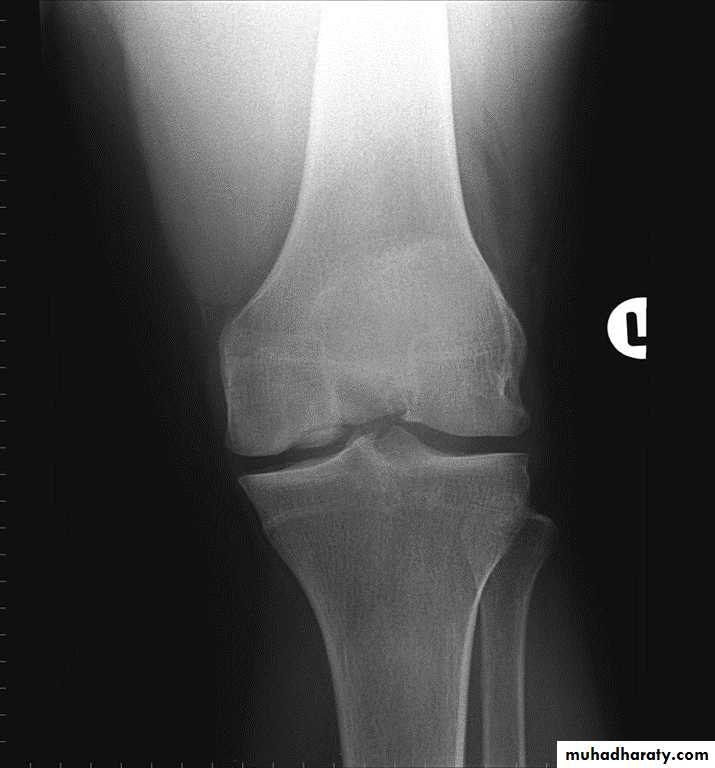

Osgood-Schlatter : 12-16 y,osteochodrosis of the tibial tuberocle.

Osgood-Schlatter disease.

Fragmentation of the tibial tuberosity